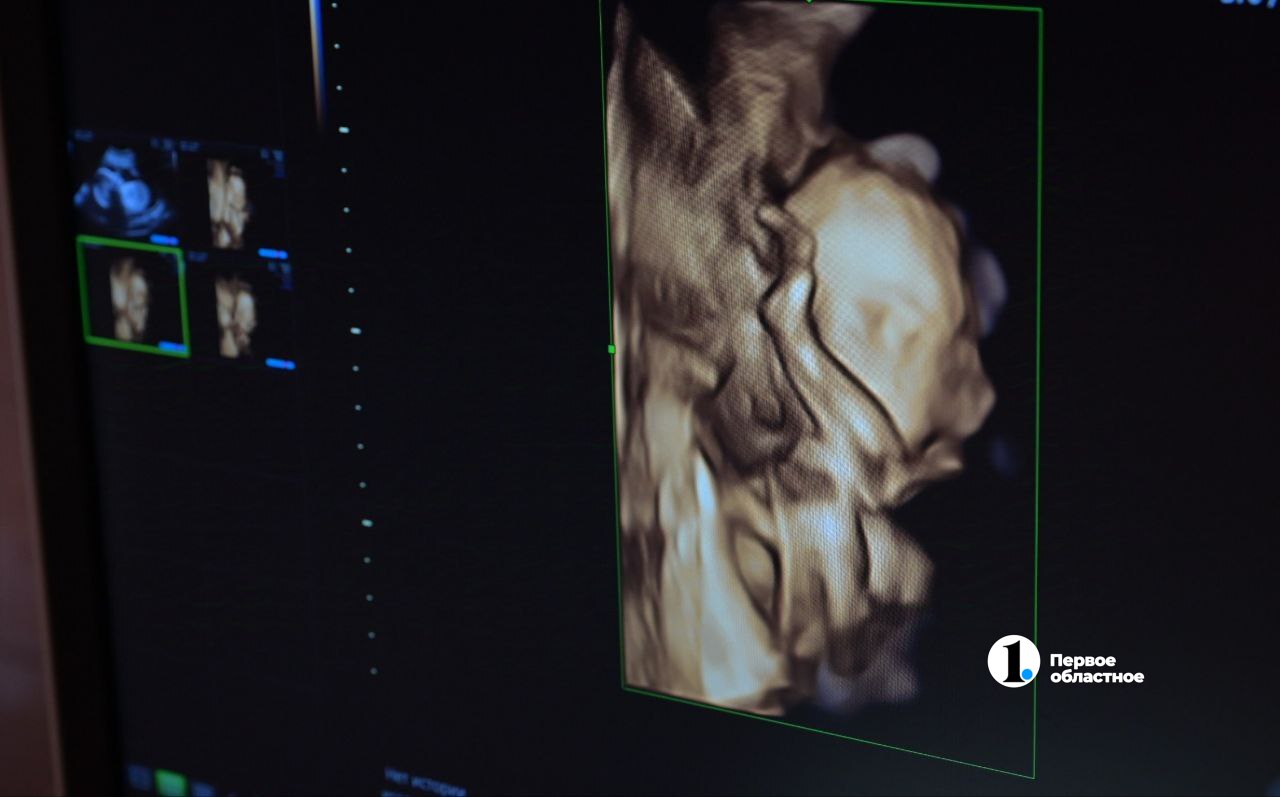

Свою профессию доктор считает самой необычной и захватывающей дух, ведь именно врач УЗИ видит, как зарождается новая жизнь, что похоже на чудо.

«Прежде всего, развиваются и растут. Некоторые детки очень спокойные — во время УЗИ они спят. Другие шевелятся, они активные. Благодаря современным технологиям мы можем увидеть, как они улыбаются, сосут пальцы, ловят ручками свои ножки, облизывают плаценту, играют с пуповиной, крутятся, вертятся, плавают. То есть делают абсолютно весь спектр движений, которые может совершать человек. Хотя удивительно: после рождения они лежат и даже не могут самостоятельно повернуться», — рассказывает Мария Токарева.